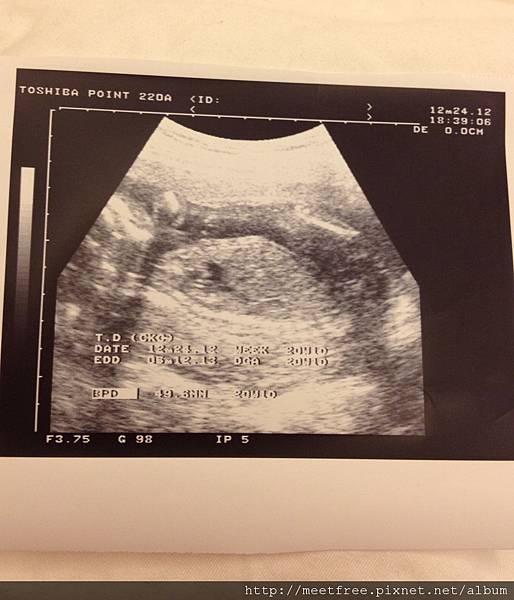

• 【媽咪日記】-第二次產檢

20W2012/12/24 Mon.(一)

耶誕夜,是第2次產檢的日子,

雖然不跟大家一樣去吃耶誕大餐,但想到可以跟駱小妞見面,

也算是另類的耶誕"禮物"吧XD

(繼續閱讀...)